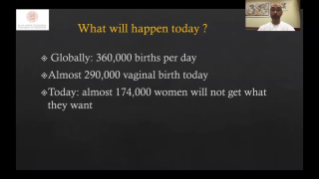

????? ??? ??? ??? ?? ?? ???? ????, ?????? ??? ?? ???? ?? ??? ??? ??? ??? ?? ???? ?? ???? ????? ???.

?? ??? ???? ??? ? ?????

??? ?? ??? ?? ???? ? ??? ?? ??? ?? ??? ??? ??? ???. ???? ??? UWN+ ?? ?? ??? ?? MI??? ??? ??? ?? ?? ??? ?? ?? ?? ???, ?? ?? ?? ???? ??? ? ????.